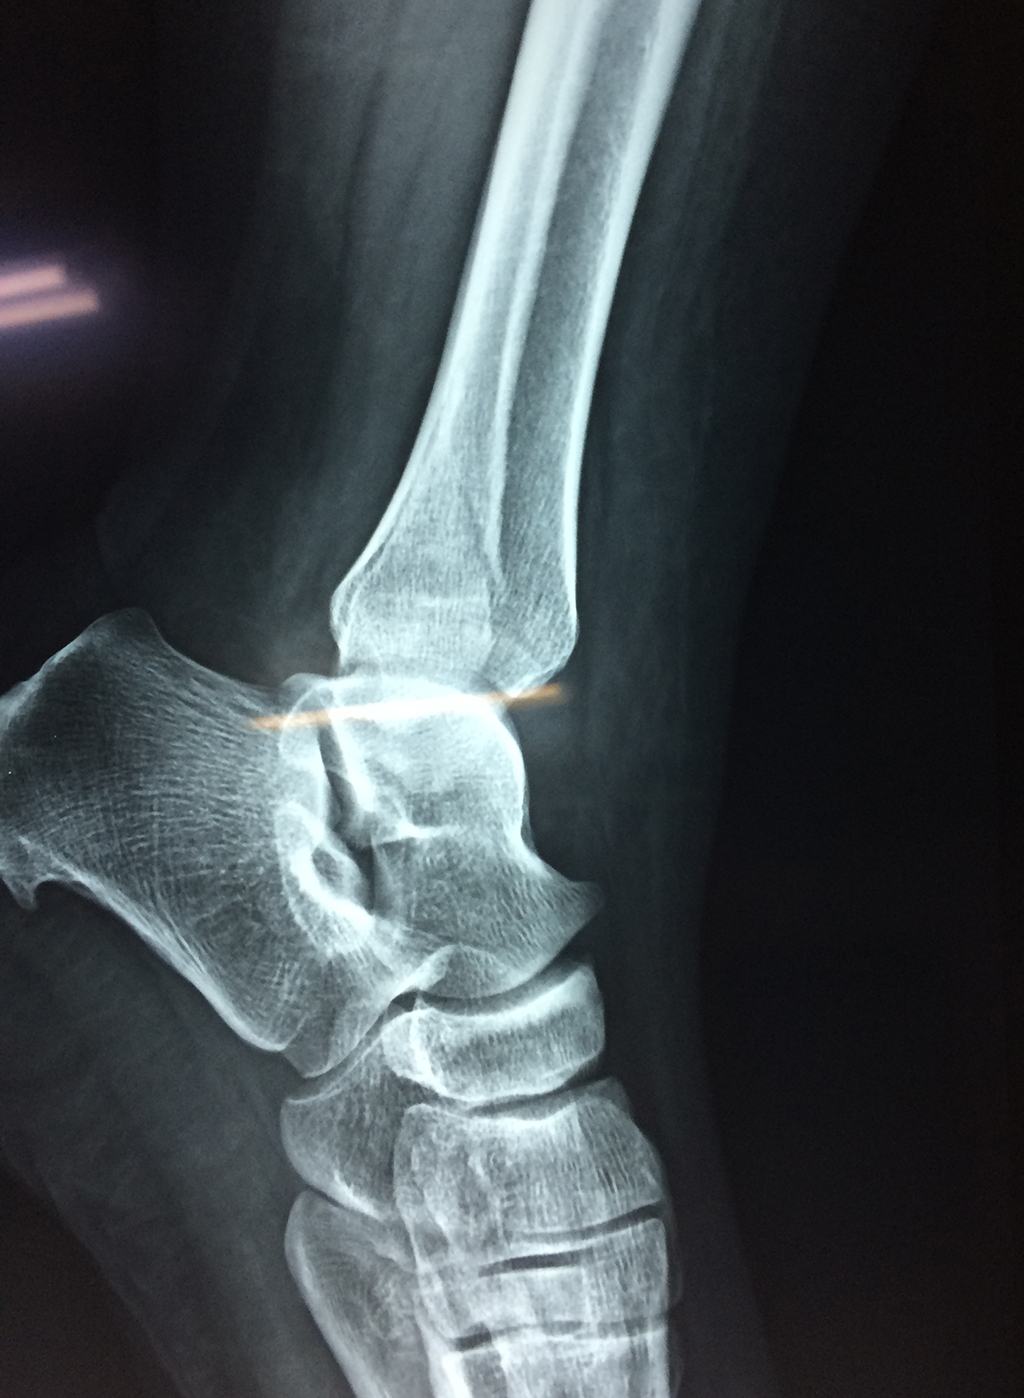

Una fractura de tobillo es la rotura de uno o más de los huesos del tobillo. Estas fracturas pueden ser:

- Los extremos de los huesos están desalineados entre sí (desplazados).

- La fractura se extiende hasta la articulación del tobillo (fractura intra-articular).